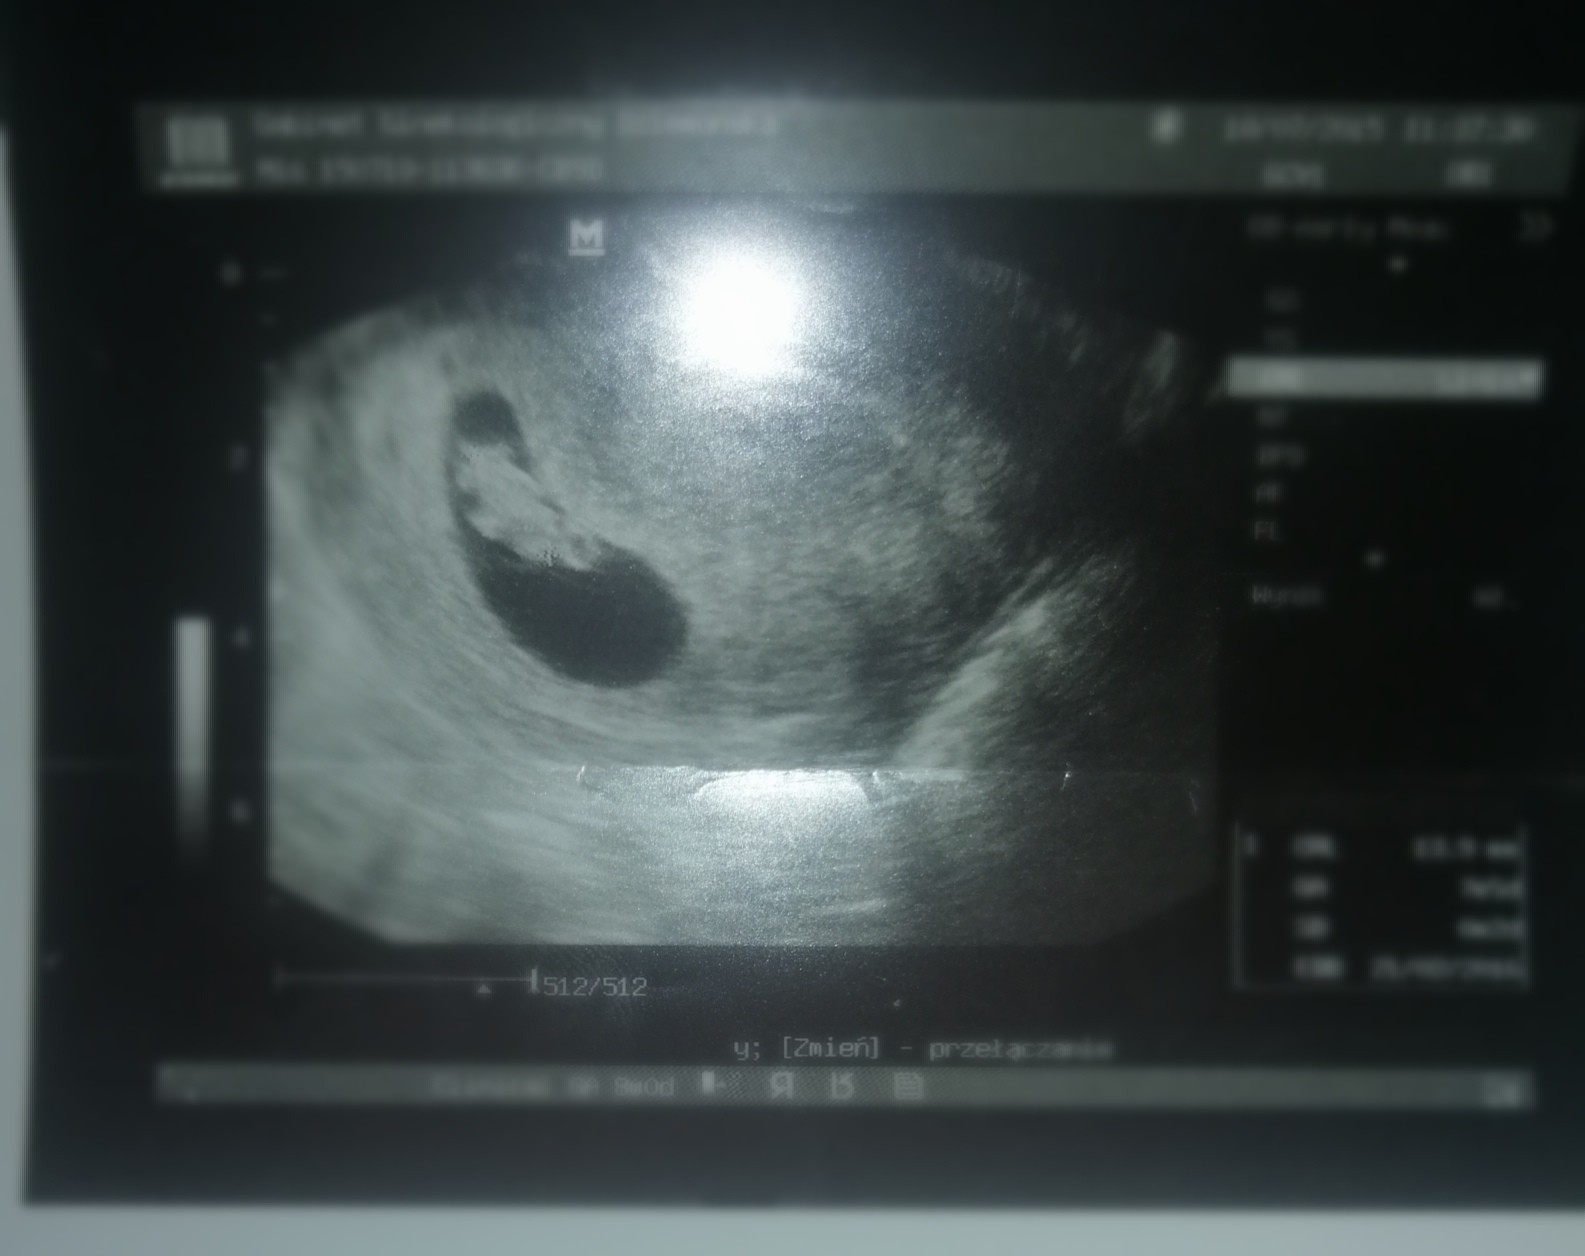

Dzień dobry, ja także dziś już po kolejnej wizycie tym razem u mojego Filipka prywatnie, serduszka nadal nie słuchałam ale nie będę narzekać, najważniejsze, że bije jak dzwon 🔔😍 mamy już 8.3mm 😊

• IMG_20210218_140818.jpg

IMG_20210218_140818.jpg

730,4 KB · Wyświetleń: 87